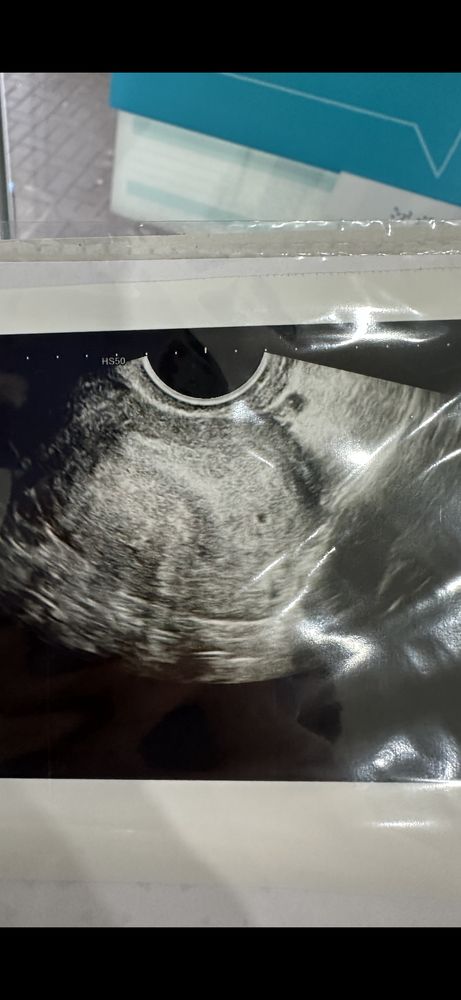

Изображение

Это скорее всего маточная беременность . Точнее плодное яйцо в полости матки . Внематочная исключена . У меня в первом протоколе похожее узи только плодное яйцо было в противоположной стороне . У меня закончилась Анэмбрионией. Пусть ваш малыш растет и развивается ❤️